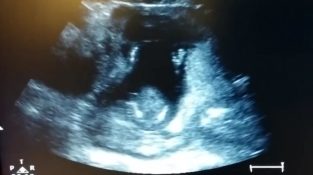

Ultrazvuk pokazuje bebu da pobedimo pljeskanje

U poseti doktora za ultrazvuk, 14-недељна трудница и њен муж приметили су да њихова беба као да ритмично маше рукама, Prebijaš pljeskanje. Приликом снимања инцидента [...]